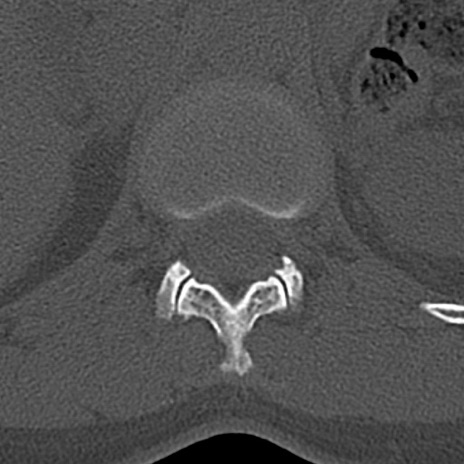

腰椎CT

横断像と矢状断像